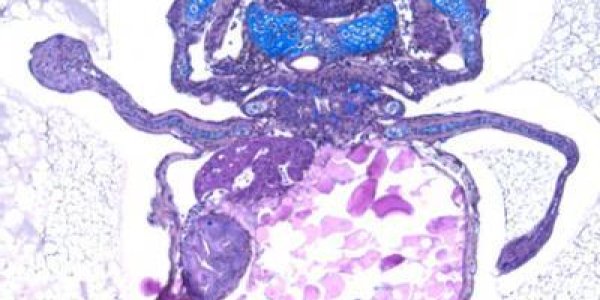

Bacteria have lived for millions of years in our planet where, with an impressive capability to adapt, they now colonize virtually every environment, including us. But as tiny one-cell organisms they…